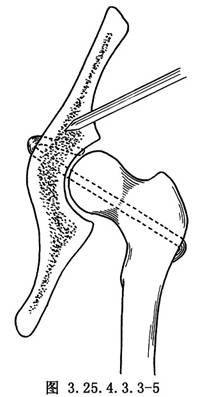

用4mm直徑斯氏針於大粗隆下緣向股骨頭中央鑽洞,將大粗隆基底帶蒂的髂脛束條縫成管狀,用有孔探針由大粗隆基底的骨洞穿入,由股骨頭中心拉出。再於髖臼中央偏前方,用骨鑽鑽洞,由髂骨內面的骨洞放入探針,將再造的圓韌帶由洞內拉出,將股骨頭復位,將圓韌帶拉緊與髖臼上緣的骨質和肌附麗再縫合固定,或於髂前下棘處鑽洞成襻狀縫合固定(圖3.25.4.3.3-3~3.25.4.3.3-6)。